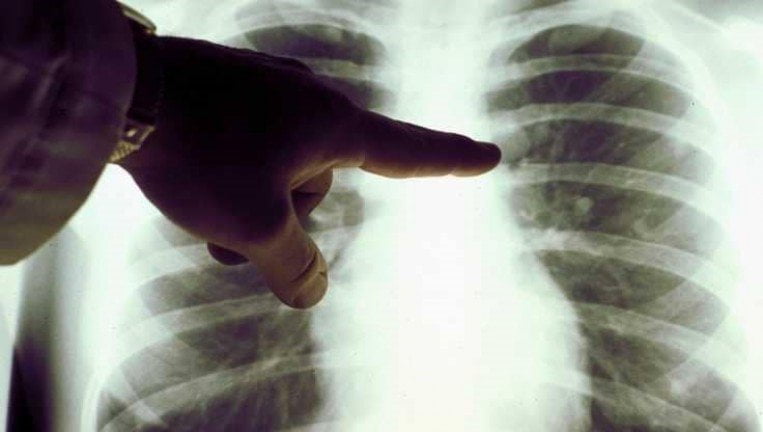

عندما نسمع عن سرطان الرئة، يتبادر إلى الذهن سريعا تدخين السجائر كمسبب رئيسي، لكن العلماء وجدوا أيضا أن بعض الأغذية يمكن أن تؤدي إلى هذا المرض الخطير.

وأظهرت دراسات علمية صدرت حديثا، أن العادات الغذائية للفرد قد تسهم كذلك في فرص إصابته بسرطان الرئة.